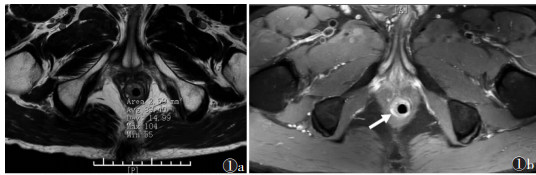

湿热下注证的主瘘管T2WI信号强度明显高于正虚邪恋证(P<0.01,图 1,2)。2组主管的内口位置、深度、长径及支管T2WI信号强度比较,差异均无统计学意义(均P > 0.05)。

| 图 1 男,26岁,复杂性肛瘘,湿热下注证 图1a T2WI上肛瘘位置测量信号强度为89.4 图1b 箭头为PDWI上瘘管位置 |